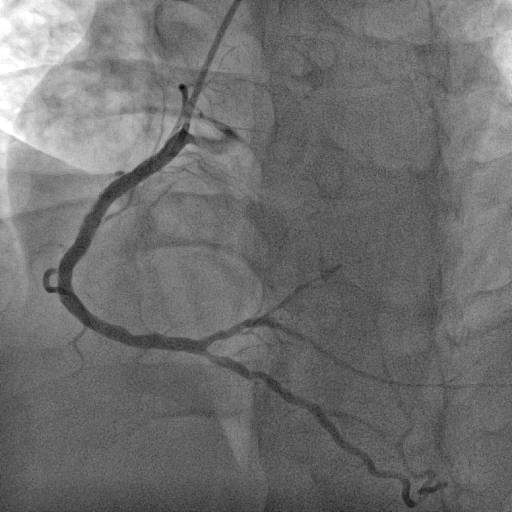

We decided to proceed with the primary percutaneous coronary angioplasty via right radial access by using the 5F JR 3.5 guiding catheter . We used Run through NS floppy wire for crossing culprit lesion to distal RCA but TIMI flow 0. We used micross 1.0 balloon for just cross the lesion and tracking balloon over the lesion . Then distal segment properly seen. Pre dilatation not done due to acute lesion and high chance of thrombus dislodgement and distal embolization . Direct stent 3.50 x 42 mm was implanted in proximal RCA to Mid RCA at 14 atmosphere pressure. Stent was well apposed and final result angiography was excellent and TIMI III flow without residual lesion and no distal embolization. the procedure done without any complications. Total Inj. heparin 10000 unit given and ACT was 298 sec.

Case Summary